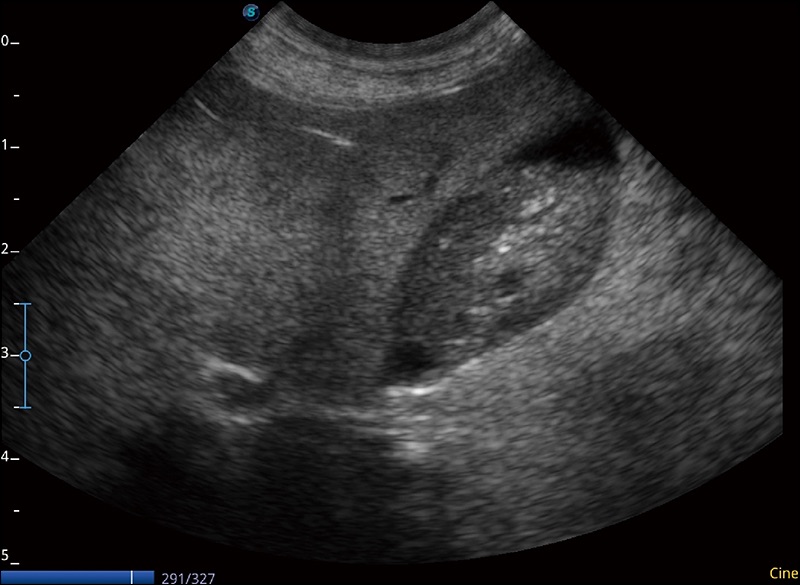

α1卓越的图像质量和便捷的工作流程,使每位宠物医生都能轻松扫查。其全面的兽用应用功能和紧凑型的结构设计,可以满足动物检查的多种需要。专业的预设检查模式和多领域测量软件包有助于为不同类型的动物提供检查, 让宠物医生能够出色的完成工作。

在不牺牲时间分辨率的情况下提供出色的图像

优化不同角度的图像